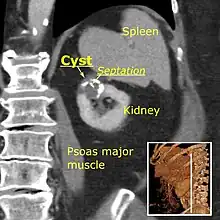

Bosniak II cyst at the lower pole of right kidney with septations within.